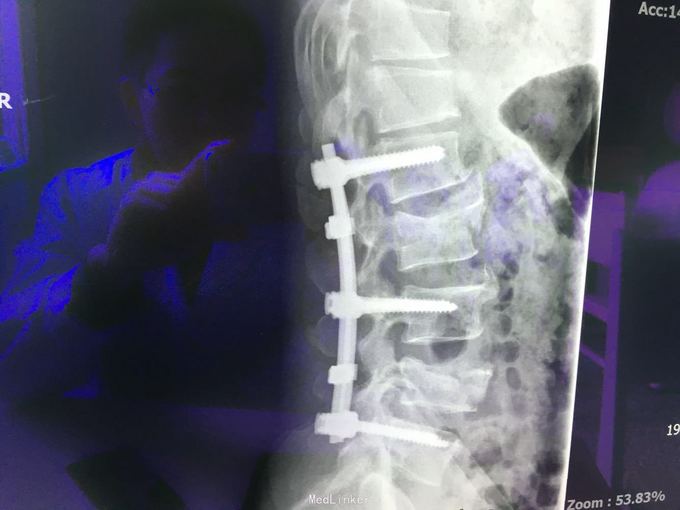

查体:左肾区叩痛,无皮肤隆起,未扪及肿块;腰椎压痛,活动受限,双下肢感觉存在,右小腿石膏托外固定,有踝关节明显肿胀,局部压痛活动受限,指端感觉血运可。 CT及X片:L2、L4椎体爆裂性骨折,L1-L4左侧横突骨折,右坐骨支骨折,右侧胫骨内、后及右侧腓骨外踝骨折,右足第1-4跖骨向外侧脱位及半脱位,伴近端斯脱性骨折。左肾挫裂伤,左肾重度积水,左肾周血肿。

诊断:右足lisfrance损伤,左肾挫裂伤;左肾周血肿,左侧输尿管结石伴左肾重度积水,L2、L4椎体骨折,L1-L4左侧横突骨折,右侧坐骨支骨折,右三踝骨折,全身多处皮肤软组织挫伤 处理:急诊行左肾探查,左肾切除术,择期行经后路腰2、4椎体骨折切开复位、椎公根螺钉内固定术+右内、外踝骨折切开复位内固定术,择期行右足lisfrance关节复位克氏针内固定术。